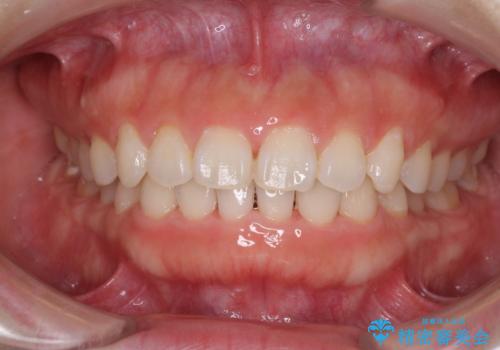

- 前歯のデコボコを治したいとのことで来院された患者様です。

上下顎ともに歯列全体の側方拡大とIPR(歯と歯の間を削る)によってデコボコが解消するように設計し、インビザラインにより治療を行うこととしました。

1日22時間の装着時間をしっかり守ってくださったので、1年程度で治療を終えることができました。

1セットのマウスピースで概ね治療を終えたのですが、前歯僅かな叢生が残ったため、2セット目のマウスピースで仕上げました。

気にしていた口元の印象が改善され、患者様には大変満足していただきました。